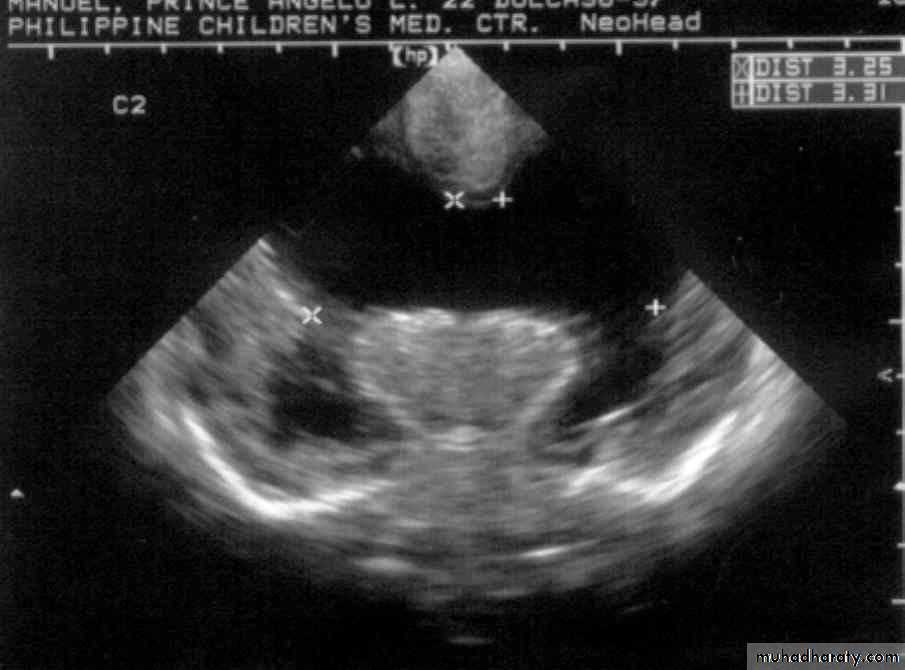

A.M., 2 months old

was noted to be microcephalic w/ szPorencephalic Cyst

SchizencephalyAbsent Septum Pellucidum

Dysgenetic Corpus Callosum

Aqueductal Stenosis